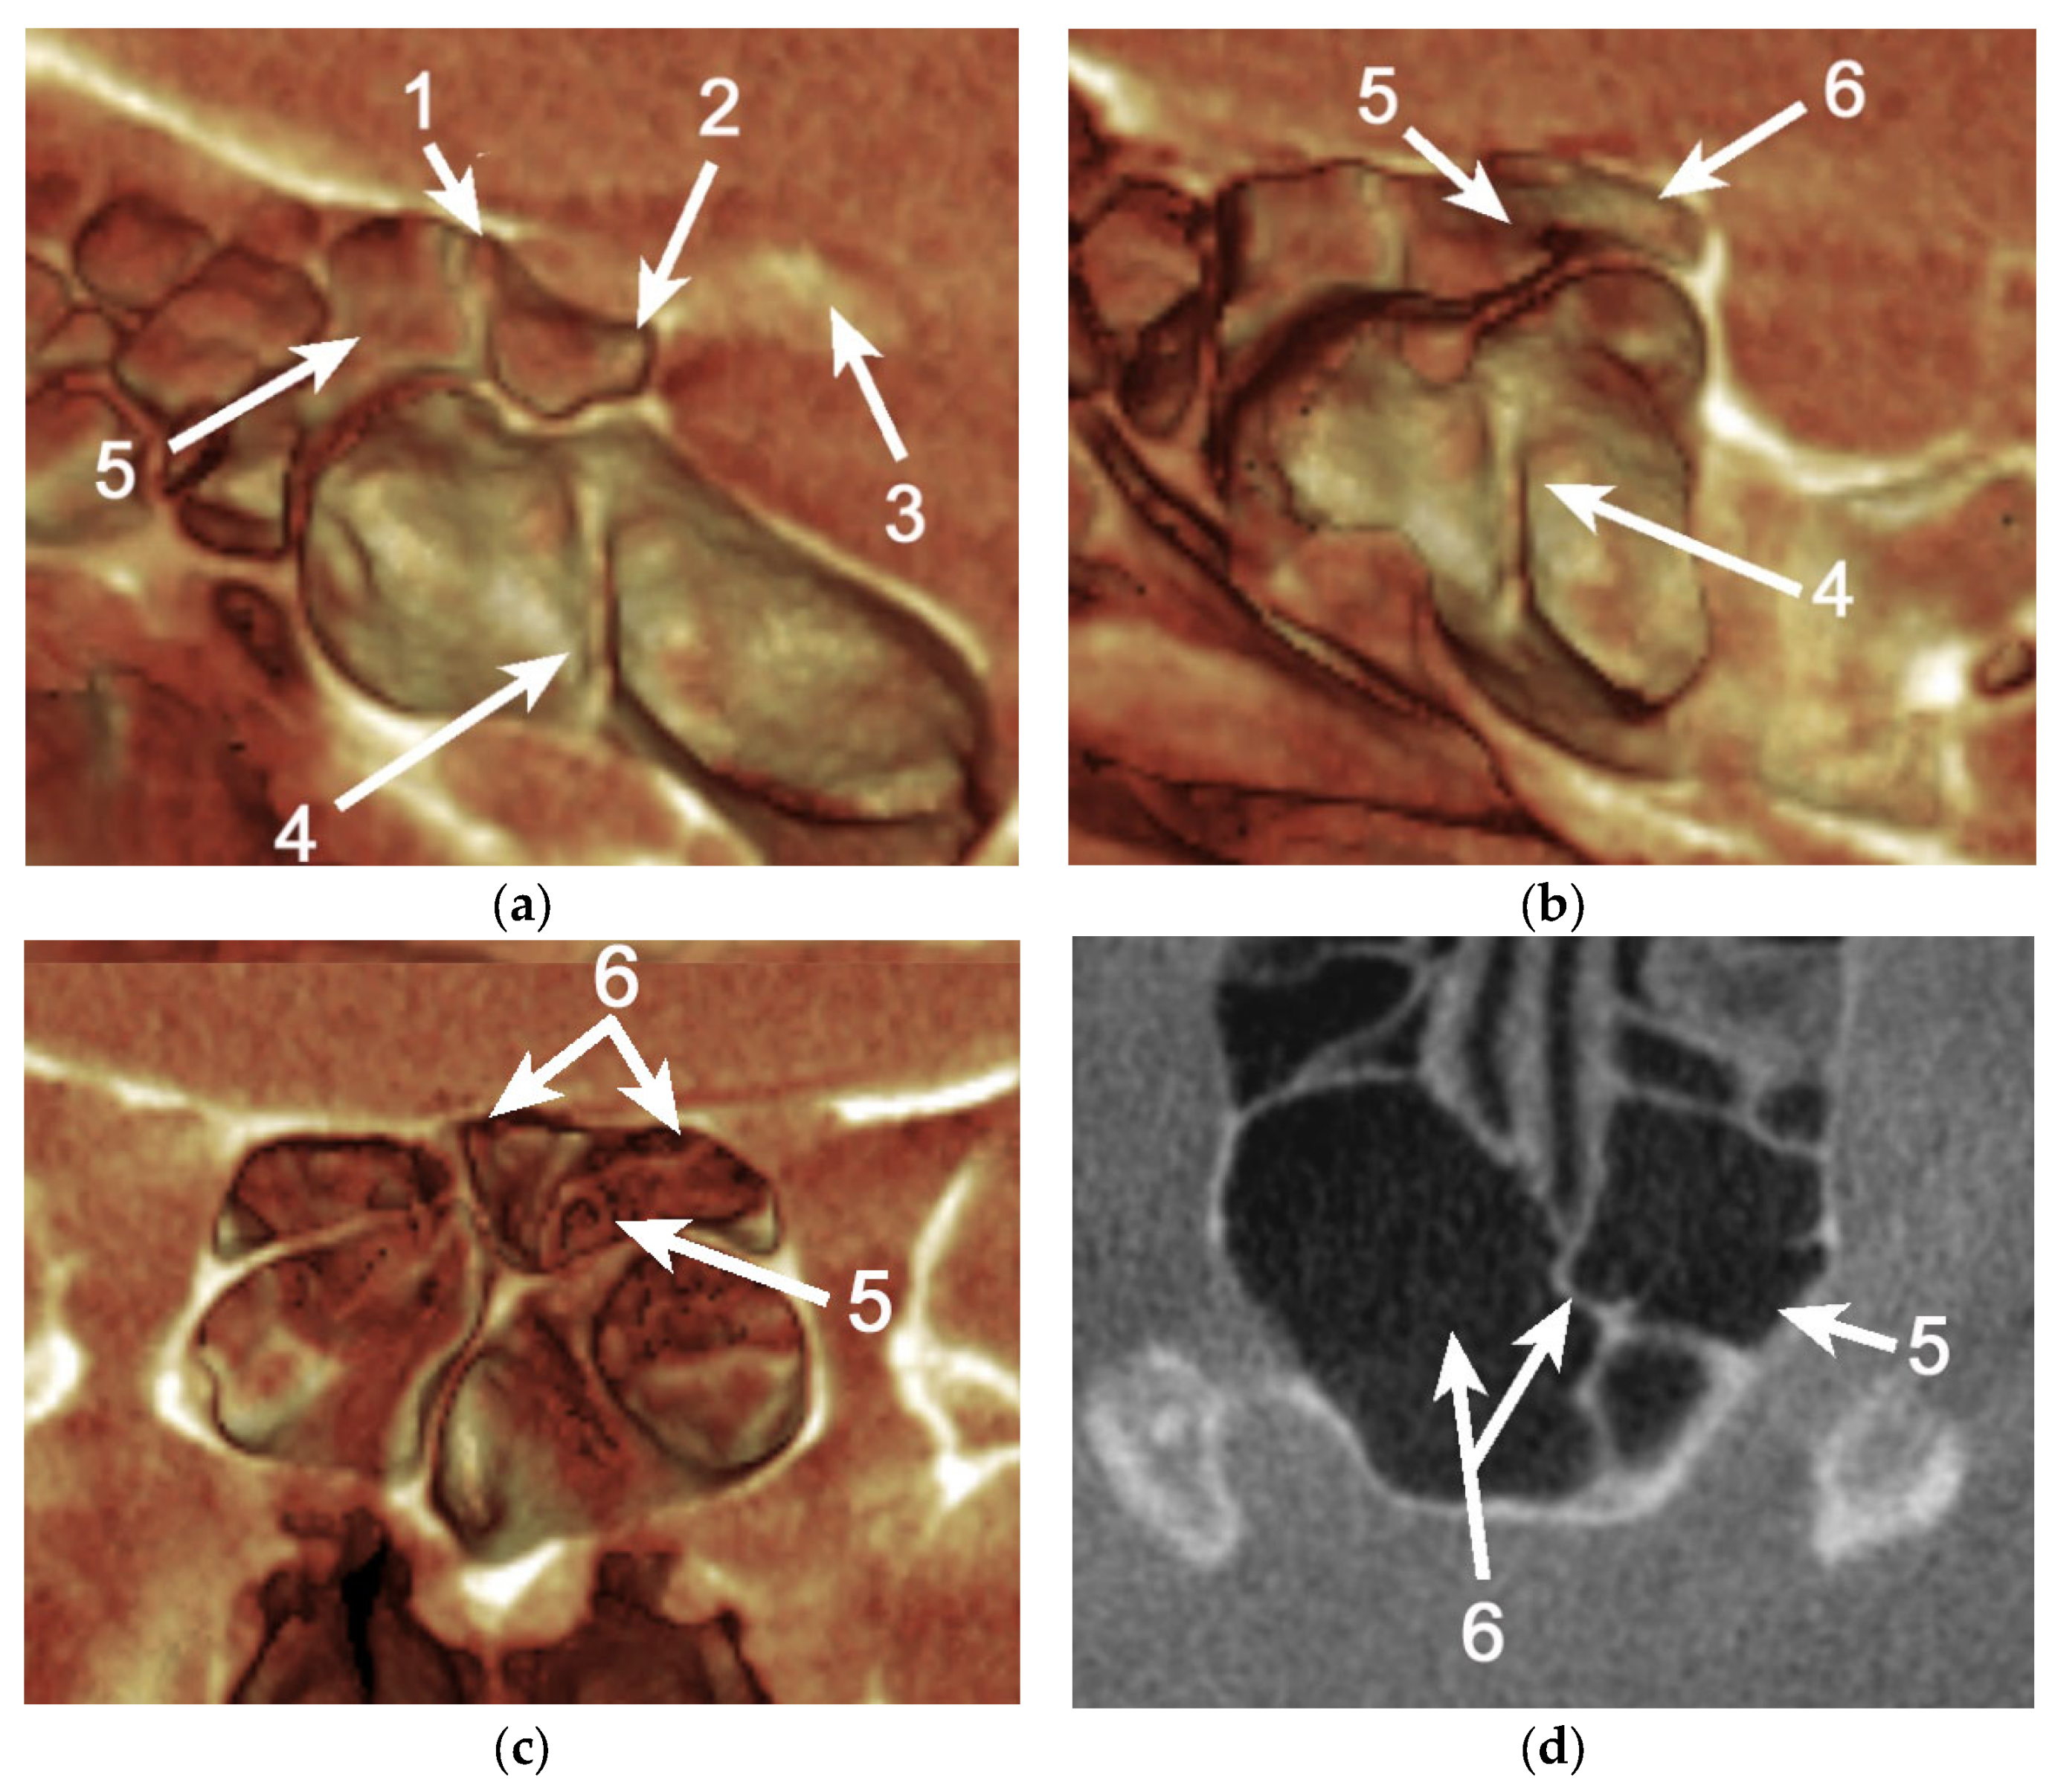

Figure 5. (a) Sagittal three-dimensional volume rendering (3DVR) of the anterior clinoid process (ACP) and paranasal air cells on the right side, which demonstrates a distinctive pneumatization of both the optic strut (OS) and anterior root (AR) of the lesser sphenoid wing, including the Onodi cell (ONC) as the origin of pneumatic cells. (b) Sagittal 3DVR of the ACP and paranasal air cells on the left side that demonstrates a pneumatization of the OS, including the ONC as the origin of pneumatic cells. (c) Coronal 3DVR of the ACP and paranasal air cells; the posterior view demonstrates a bilateral pneumatization of the planum sphenoidale (PS), with ONC as the origin. (d) Axial CBCT reconstruction at the level of the pneumatized OS. 1. Pneumatized AR; 2. Pneumatized OS; 3. ACP; 4. Sphenoid sinus; 5. ONC. 6. Pneumatized PS.

Additionally, to our knowledge, the patterns of origin for OS pneumatization were poorly evaluated, and there was no mention of ONCs as the source for it (Table 4). An important finding of the present study was the pneumatization of both the OS and AR from ONCs (11.62%). This possibility constitutes the principal cause of risk for developing orbital complications, especially in patients with ethmoiditis [9,10]. Another incidental finding while conducting the present study was the possibility that an ONC could extend within the planum sphenoidale (Figure 5). This might explain why olfactory dysfunctions, such as anosmia or hyposmia, can occur in chronic rhinosinusitis [11,12].